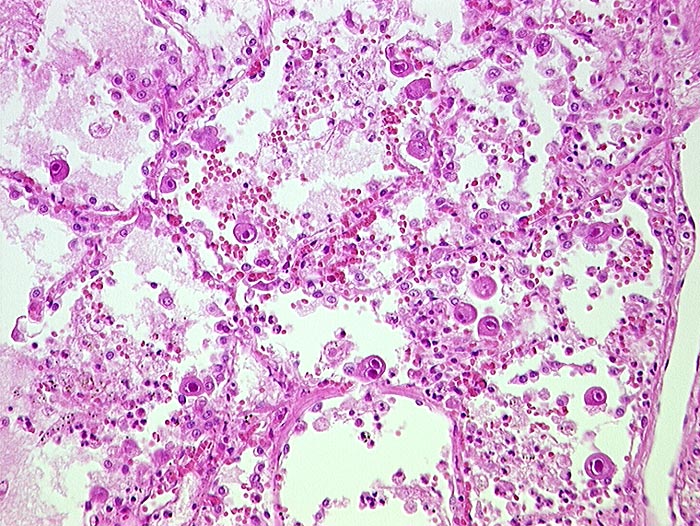

AP/ Cytomegalievirus-Infekt der Lunge

Cytomegalievirus-Infekt der Lunge

Entzündung infektiös

Lunge, Mediastinum mit Thymus

Lunge